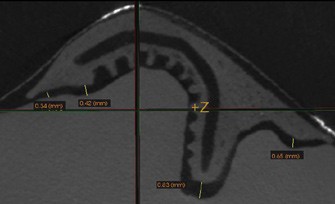

Fig 3. A 3D printed scaffold was designed using CAD software to fit a peri-osseous defect in a human patient. The scaffold consisted of a region with channels designed to support oriented PDL tissue formation and a region for the regeneration of osseous tissue. Fig 3: baseline;

Fig 4: defect model; Fig 5 through Fig 7: internal, tilted, and side views of scaffold, respectively; Fig 8 through Fig 10: coronal, middle, and apical

angles, respectively; Fig 11: cross-section diagram; Fig 12: labial scan image. (Images reprinted with permission from Rasperini G, Pilipchuk SP, Flanagan CL, et al. J Dent Res. 2015;94[9 suppl]:153S-157S.)

Synthetic polymers such as polycaprolactone (PCL) and poly-L-lactic acid (PLA) can be combined with natural polymers such as hydroxyapatite and β-tricalcium phosphate to allow the formation of biphasic constructs with tailored mechanical properties and rates of degradation. Recently, a first-in-human case report of a custom-designed, 3D-printed PCL scaffold for the treatment of a large periodontal defect was reported in combination with PDGF administration (Figure 3 through Figure 20).23 The scaffold was fabricated using selective laser sintering, which allowed for material powder to be fused together to form a structure based on a CAD file of the scaffold that was designed from CBCT scans of the patient defect. This novel approach offers a promising future application of 3D printing for customized scaffold designs that can be tailored to meet patient-specific needs based on defect site and location, with the added ability to deliver growth factors.